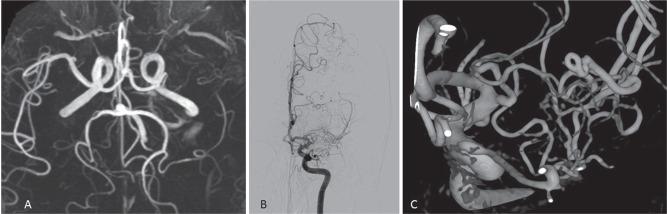

There are several anomalies of the middle cerebral artery (MCA) in humans, such as accessory MCA, duplicated MCA, fenestration of MCA, and duplicated origin of MCA. Recently, unfused or twig-like MCA, which indicates MCA trunk occlusion with collateral plexiform arterial network, have been reported. During the embryonic stage, MCA is thought to generate from plexiform arterial twigs arising from the anterior cerebral artery, and these twigs form the definitive MCA by fusion and regression at the end of the development stage. Any interruption during the fusion of the arterial twigs may result in MCA anomalies, and the unfused or twig-like MCA, especially, is hypothesized to be the persistent primitive arterial twigs. Clinically, it is challenging to differentiate the unfused or twig-like MCA from unilateral moyamoya disease, in which stenotic change begins at the MCA. The knowledge of the anomalies of the MCA is important to perform a safe surgical or endovascular intervention.

人类大脑中动脉(MCA)存在多种异常情况,如大脑中动脉副支、大脑中动脉重复、大脑中动脉开窗以及大脑中动脉起源重复。最近,有报道称出现了未融合或树枝状大脑中动脉,这表明大脑中动脉主干闭塞并伴有侧支丛状动脉网络。在胚胎阶段,大脑中动脉被认为由大脑前动脉发出的丛状动脉小支发育而来,这些小支在发育阶段末期通过融合和消退形成最终的大脑中动脉。动脉小支融合过程中的任何中断都可能导致大脑中动脉异常,尤其是未融合或树枝状大脑中动脉,被推测为持续存在的原始动脉小支。临床上,将未融合或树枝状大脑中动脉与单侧烟雾病区分开来具有挑战性,单侧烟雾病的狭窄改变始于大脑中动脉。了解大脑中动脉的异常情况对于进行安全的外科手术或血管内介入治疗很重要。